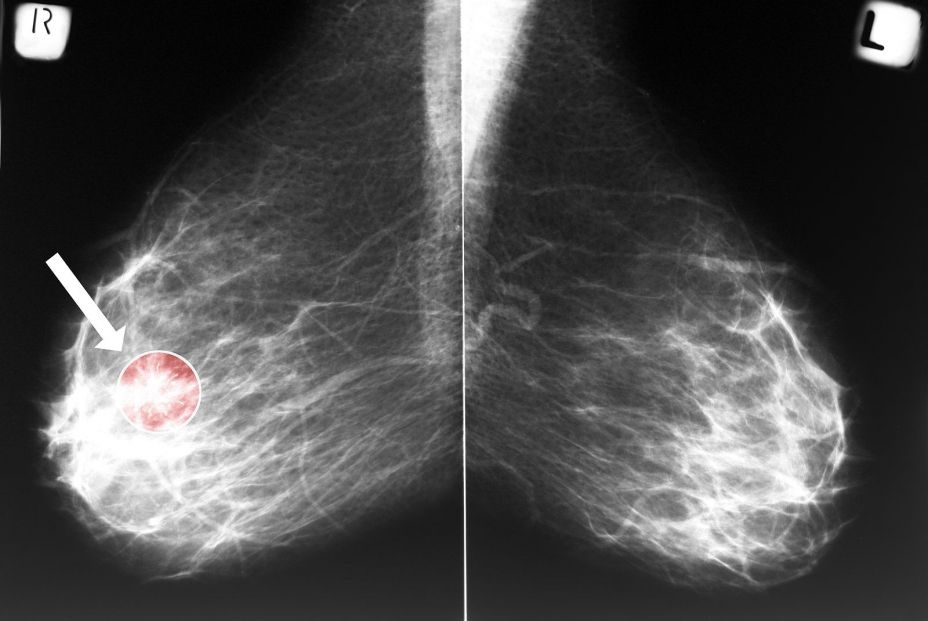

La interpretación de las mamografías de cribado es uno de los temas más estudiados en medicina. Detectar cánceres de mama sin tener que volver a citar a un número excesivo de mujeres para estudios de seguimiento es un equilibrio complejo. Los radiólogos de mama se esfuerzan por lograr una alta sensibilidad y, al mismo tiempo, mantener una especificidad razonable. Con la mamografía, se detectan de tres a cinco cánceres por cada 1.000 mamografías en la población sana, pero algunos cánceres de mama pasan desapercibidos.

Como documenta un estudio de Radiology, el tejido mamario denso es una de las principales causas de que no se detecten los cánceres. Los cánceres de intervalo (CI) son aquellos que se diagnostican después de una mamografía de cribado negativa, pero antes de la siguiente ronda de cribado.

Representan tumores no detectados (falsos negativos) o cánceres nuevos. Los CI tienen un peor pronóstico que los detectados mediante cribado, y minimizar su número es un gran objetivo. Cuando se utilizan herramientas de inteligencia artificial (IA) en la obtención de imágenes mamarias, al igual que con los ‘lectores humanos’, se debe lograr un equilibrio entre la detección del cáncer de mama y la minimización de falsos positivos. Los algoritmos de IA pueden utilizarse para ayudar al radiólogo en la interpretación, para actuar como un lector doble o incluso como una modalidad independiente, como se recoge en una investigación del Journal of Clinical.